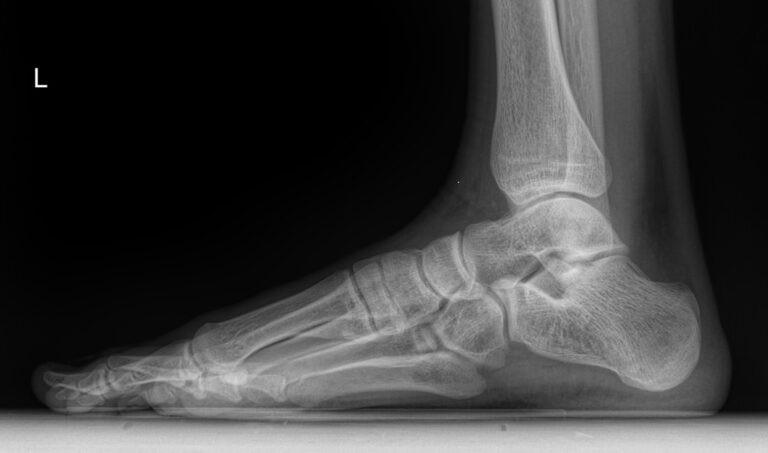

В качестве диагностической процедуры для выявления плоскостопия часто используют рентген. Прицельное исследование стопы позволяет увидеть изменения в ее строении, а также вычислить угол и высоту свода стопы, показатели которых используются для установления стадии болезни.

На снимке будут отчетливо видны:

• Кости предплюсны;

• Наложенные друг на друга кости плюсны;

• Травмы, в том числе застарелые;

• Патологические изменения видимых суставов;

• Опухоли.

Рассчитывается высота и угол свода стопы и соответствующая им степень плоскостопия.

Никакой подготовки не требуется. Пациент оголяет ногу ниже колена и ставит ее на пластину детектора. При этом вес тела переносится на исследуемую ногу. Жизненно важные органы закрываются защитным фартуком. Съемка выполняется в боковой проекции и идет 1-2 секунды, во время которых важно не шевелиться.